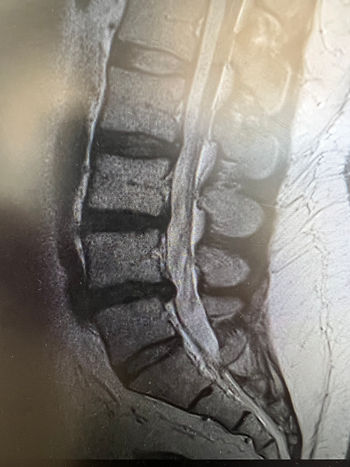

La discectomía percutánea, como toda técnica quirúrgica tiene sus indicaciones y pacientes “candidatos”. Entre ellas, se encuentra el/la paciente joven con un dolor lumbar y un disco vertebral relativamente conservado y/o una hernia discal “contenida”, es decir, que no ha migrado hacia arriba o abajo (imagen adjuntada a continuación).